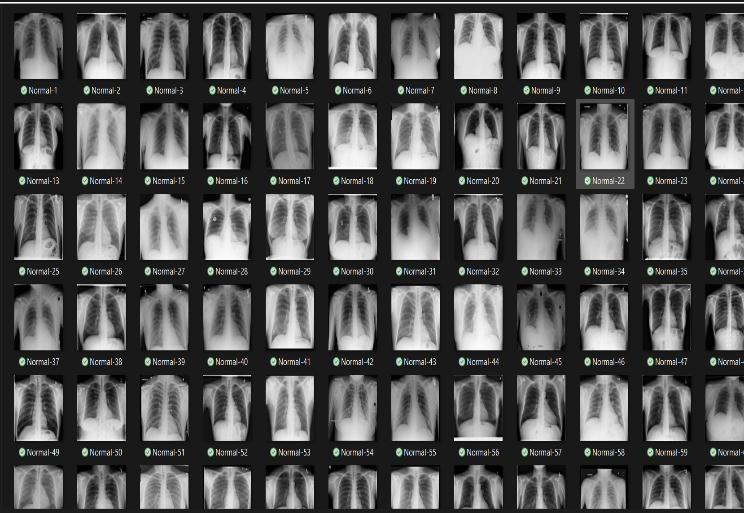

A. DATASET UPLOAD

ItistheUIofthewebpagewhichcontainssingleupload button.Thispagecollectstheuploadedimageandgiveitas theinputforthedetectionmodel.

A UI (User Interface) containing a single upload button can be a simple and effective way to collect chest X-ray images from users for TB detection using the proposed cloud-basedwebapplication.

The UI can consist of a single web page with a clear and prominent "Upload Image" button. When the user clicks the button, they will be prompted to select a chest X-ray image file from their local device. Once the image is selected,itwillbeuploadedtothecloud-basedserver,and thedetectionmodelwillbetriggeredtoprocesstheimage.

The UI can also include a progress bar or loading animationtoprovidefeedbacktotheuserwhiletheimage isbeinguploadedandprocessed.Oncethedetectionmodel has processed the image, the UI can display the results of the TB detection, indicating whether the image is TBpositiveorTB-negative.

Overall, a simple and intuitive UI with a single upload button can enable easy and efficient collection of chest XrayimagesfromusersforTBdetectionusingtheproposed cloud-basedwebapplication.

Fig-1AlgorithmBlockDiagram Fig-2 UploadingX-RayImageinwebApplication